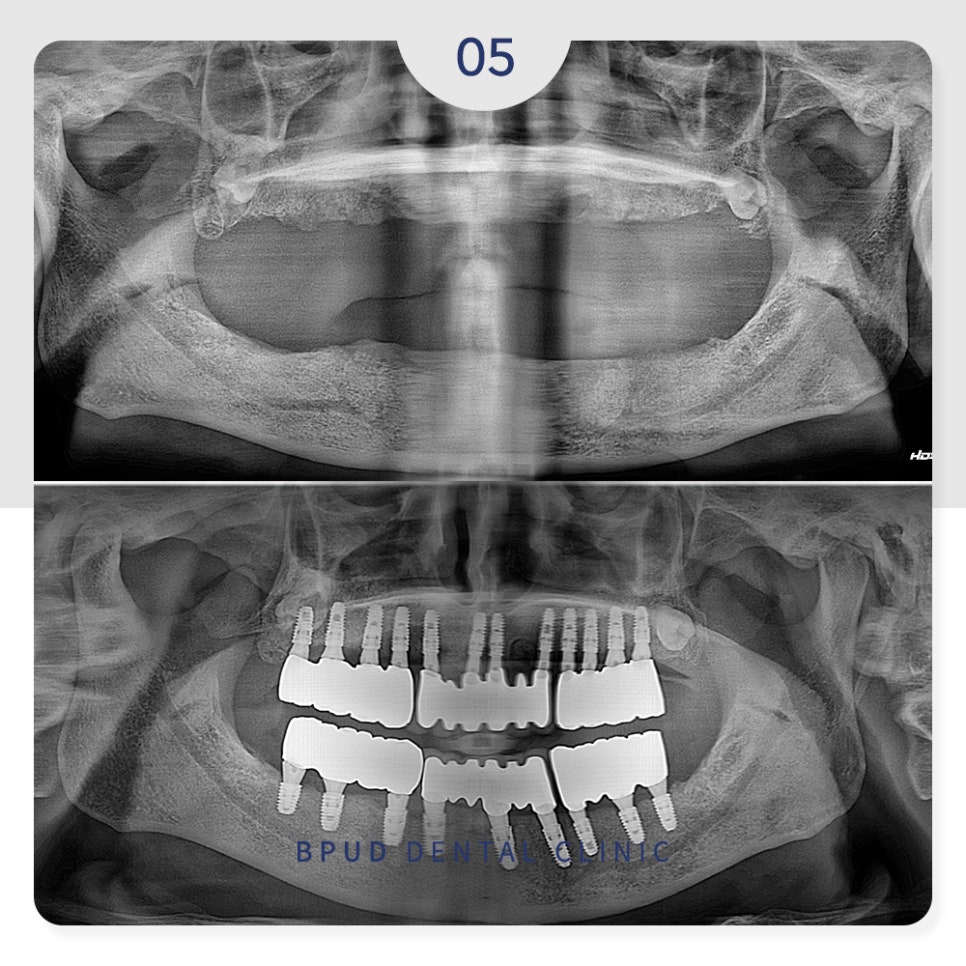

23.06.05

오늘은 오랫동안 전체 틀니를

사용하시다가 부평치과 전체임플란트로

교체하신 환자분을 소개해 드리겠습니다.

전체적인 수복을 원하셨기 때문에

3D CT를 통한 면밀한 진단을 통해

위쪽 12개, 아래쪽 9개의 임플란트를

수복하기로 계획을 수립하였는데요.

아래쪽은 신경의 위치를 고려하여

작은 어금니 부위는 인공치아로 대체하였고

오랜 기간 틀니의 사용으로

전체적으로 많이 흡수가 진행된

잇몸뼈는 치조골 이식을 통해

회복하기로 하였습니다.

식립할 개수가 많다 보니

위쪽 먼저 식립하고 일주일 뒤

아래쪽을 진행하였는데요.

23.06.12

아래쪽까지 식립을 마친 후에는

잇몸뼈와 인공치근이 단단하게

융합되는 기간으로

약 4~5개월 동안 임시틀니를

제작하여 사용하실 수 있도록 하였습니다.

24.01.23

최종 보철물까지 완성하고 난 후에는

틀니보다 훨씬 편하고 심미적이어서

환자분의 만족도는 매우 높으셨습니다.